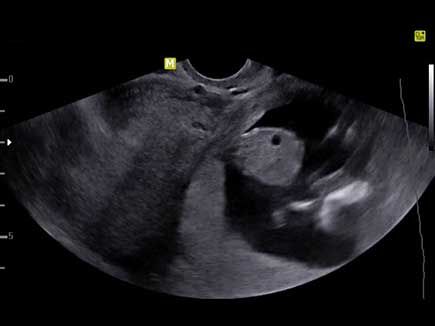

A routine ultrasound exam of a 28-week fetus revealed what looked to be a cystic lesion. The addition of Doppler, however, changed the diagnostic picture.